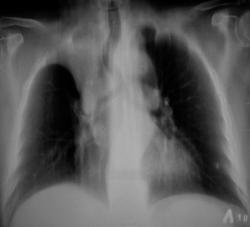

Хотелось бы узнать возраст, клинику, ну и жалобы неплохо было бы. "Попахивает" ателектазом. Мне показалось, что срединная тень сместилась немного вправо, да и контуры затенения уж очень ровные.

Да, тянет на ателектаз, хотя образование может расти и из апикальной плевры, оттесняя легкое. Бронхоскопия.

Образование, деформирующее нижнюю треть трахеи справа с её оттеснением, вероятно из ВДБ, бисегментарный ателектаз. Прямые томограммы корней, стандартные боковые справа через корень. На томограммах "порезал" бы и задние отрезки рёбер.

Ателектаз верхней доли за счёт образования,которое перекрыло верхнедолевой бронх, смещает главный бронх и трахею.

По данным рентгенологического исследованинаиболее вероятна опухоль правого главного бронха с вовлечением регинальных лимфоузлов.

диагноз будет верифицирован после бронхоскопии. Но, так как у нас идет мозговой штурм по представленным данным классической рентгенографии, выскажу свой генез заболевания у больной. Наличие кальцинатов в легких и во внутригрудных лимфатических узлах с обеих сторон позволяет предположить реактивацию туберкулезной инфекции с развитием туберкулеза внутригрудных лимфатических узлов, активного туберкулеза бронхов со стенозом 3 степени и ателектаза. Такова моя версия. В ПТД сначала, а не к онкологу, чтобы не вызывать стресс у больной.

Я бы не стал изобретать велосипед и отправил бы к онкологам на бронхоскопию. Камни, бронхиолиты не дают полицикличные дефекты на контуре трахеи и бронха на томограммах, как мне думается. Плюсом пакеты внутригрудных лимфоузлов. Навязывать мнение не смею.